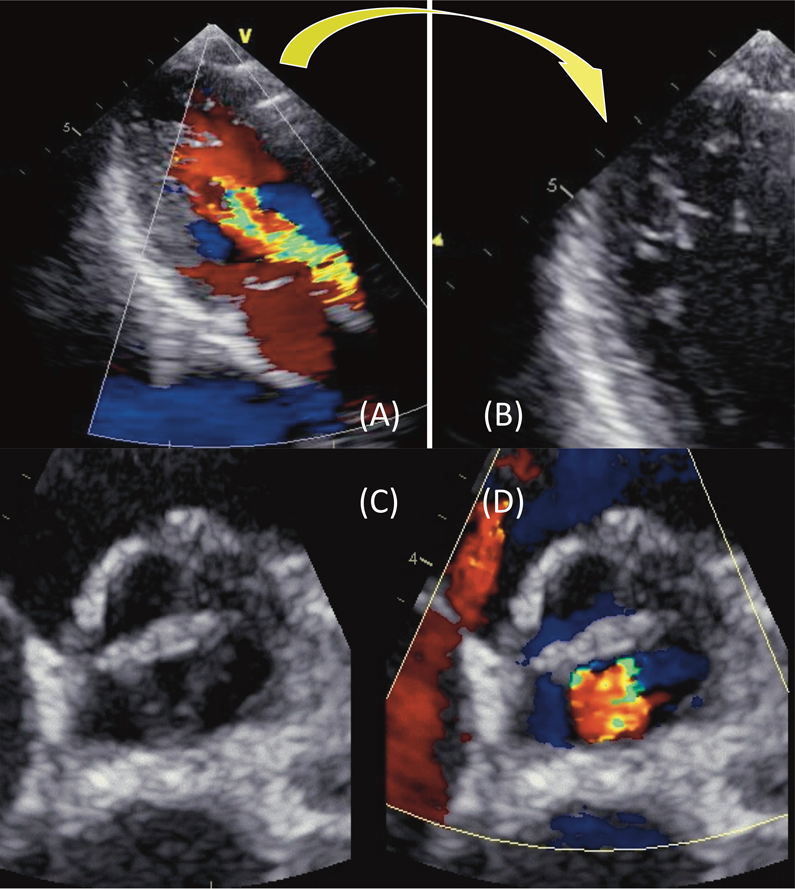

左室拡張末期径/収縮末期径= 57/38 mm,左室駆出率60%,大動脈弁中央から中程度~重度の大動脈弁逆流を認めた.大動脈弁は3尖であり,各弁尖の肥厚が著明であった.大動脈弁輪径は21 mm,バルサルバ洞28 mm, sinotubular junction(STJ)20 mm.また,軽度の左室緻密化障害が疑われた(Fig. 2).

Fig. 2 Ultrasound echocardiography

(A) The moderate to severe aortic regurgitation was shown in the long-axis view. (B) The left ventricular noncompaction was suspected on the apex. (C) All the three cusps were thickened and retracted, and the coaptation was insufficient. (D) The regurgitant flow emerged through the central triangle gap.